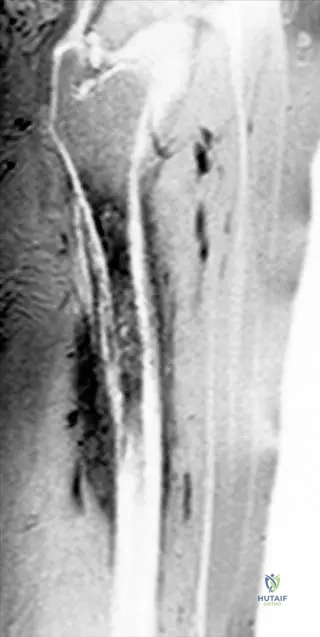

Rationale: The context for Fig. 2.5 explicitly states that "metastatic purulent foci are present in the brain and the lung (arrows), causing a life threatening condition" in the same patient with Lactococcus osteomyelitis. Neurological symptoms and respiratory distress are consistent with these metastatic foci. Main Distractor Rationale: Direct extension of femoral osteomyelitis to the spinal cord (A) is anatomically highly improbable and not supported by the case description.

Rationale: Fig. 2.5 a–c, which describes the same patient with *Lactococcus*-osteomyelitis, shows cranial MRI with metastatic purulent foci in the brain and a chest CT scan with metastatic purulent foci in the lung. These metastatic foci are described as causing a life-threatening condition. Therefore, the new neurological and respiratory symptoms are highly suggestive of systemic spread of the infection. While chronic osteomyelitis (B) can develop, it typically doesn't present with acute, life-threatening systemic symptoms. Antibiotic side effects (A), allergic reactions (D), or superinfection (E) are less likely to explain the specific pattern of brain and lung involvement seen in the images.

Correct Answer: C